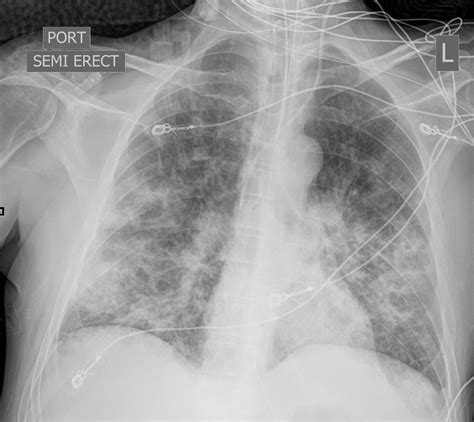

• Interstitial Infiltrates: Often associated with viral or atypical pneumonia (such as Mycoplasma pneumoniae), this appears as fine, lace-like (reticular) markings throughout the lungs, focusing on the interstitial space rather than the alveoli.

Interstitial Viral, Atypical Fine, reticular or ground-glass opacities.

• Pulmonary Edema: Fluid buildup due to congestive heart failure often presents with bilateral opacities, which can mimic bronchopneumonia.